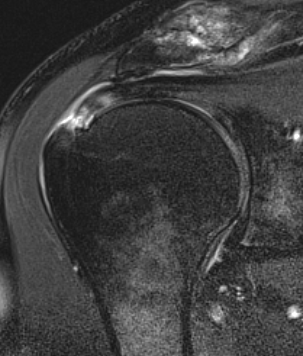

Bursal Sided